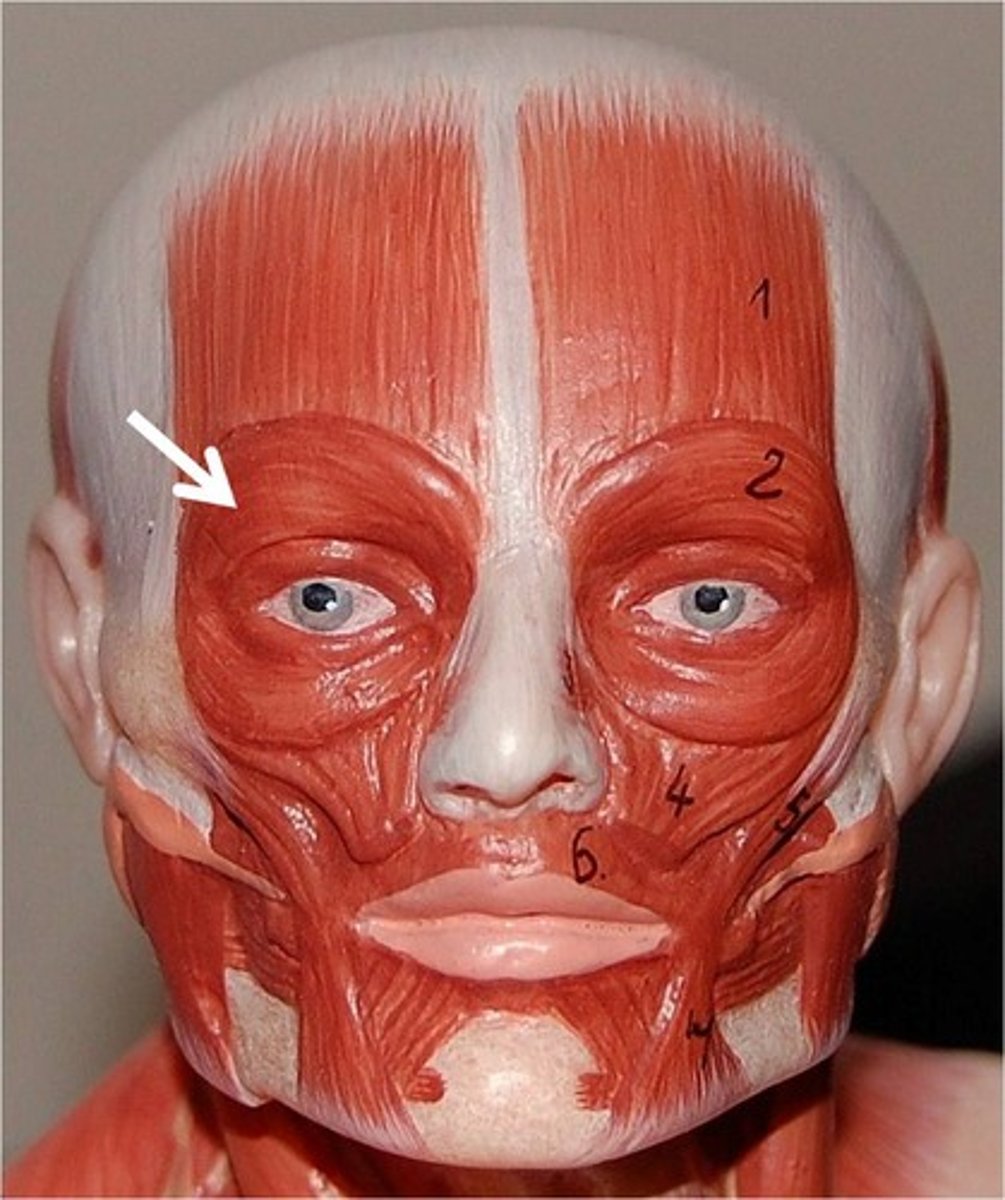

Orbicularis Oculi

Closes the eye

Orbicularis Oris

closes lips

Temporalis

Elevates and retracts mandible